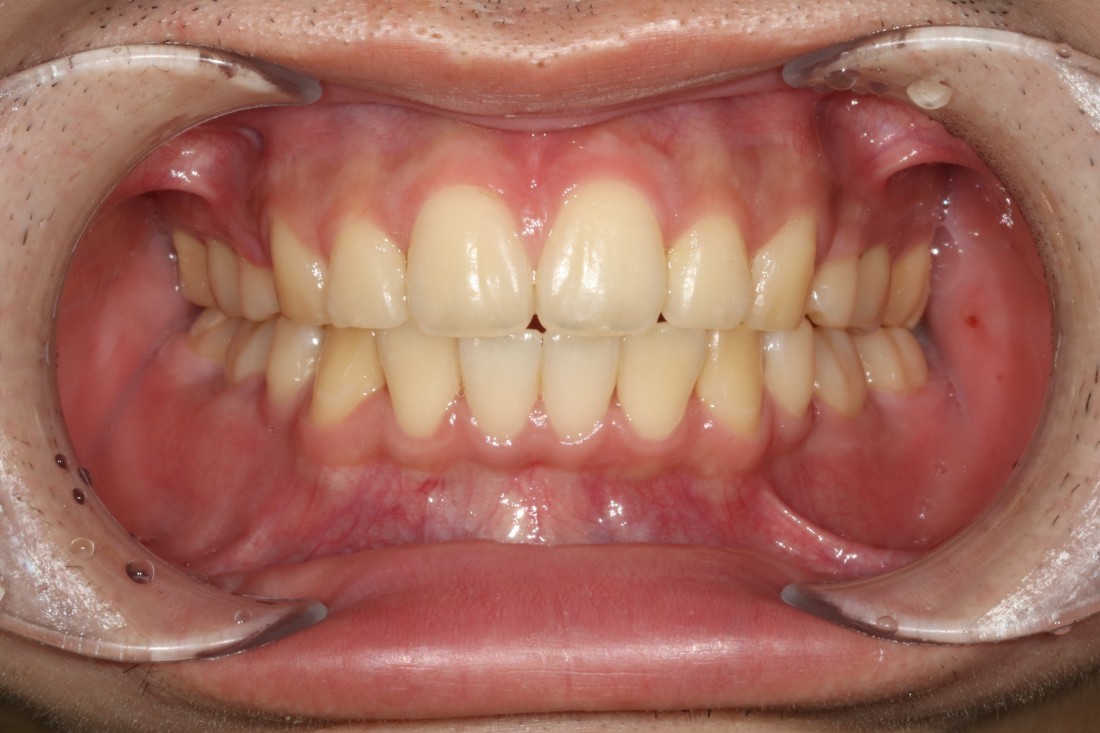

수많은 개방교합 교정 케이스를 보유하고 있으며,

교정 전/후 사진을 다양하게

홈페이지에 공유해드리고 있으니

광주 개방교합 치과의 실력을 믿으셔도 좋습니다.